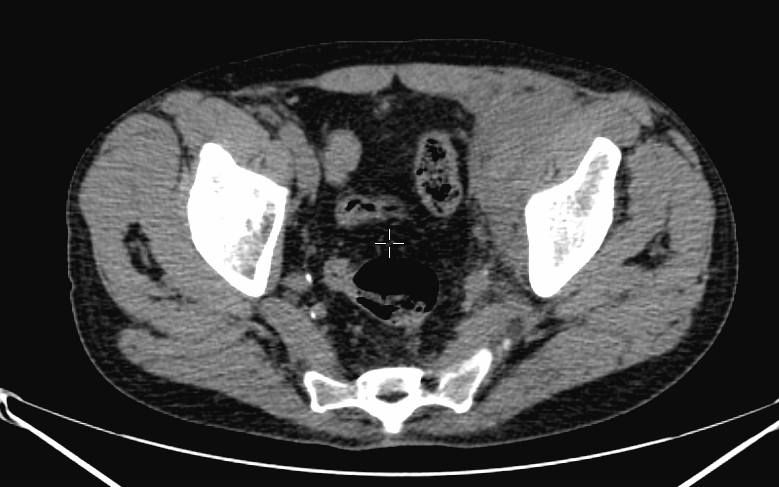

Image

a

b

c

d

e

4. Bone scintigraphy, prostate cancer. The image set shows the characterization of multiplex increased activity uptake. Posterior whole body scan (a). SPECT-CT coronal fusion images (b,d), CT examination (c,e). Sclerotic lesions in the pelvic bones are suggestive of osteoplastic metastases (b,c), small joint arthrosis at LIII-IV segments, more expressed on the left side (b,c), spondylosis on the right side at LIV-V segments (d,e). (The increased activity spot on the whole body scan, at the left cubital region, is correspondent to the paravasation of the iv. radiopharmaceutical.)